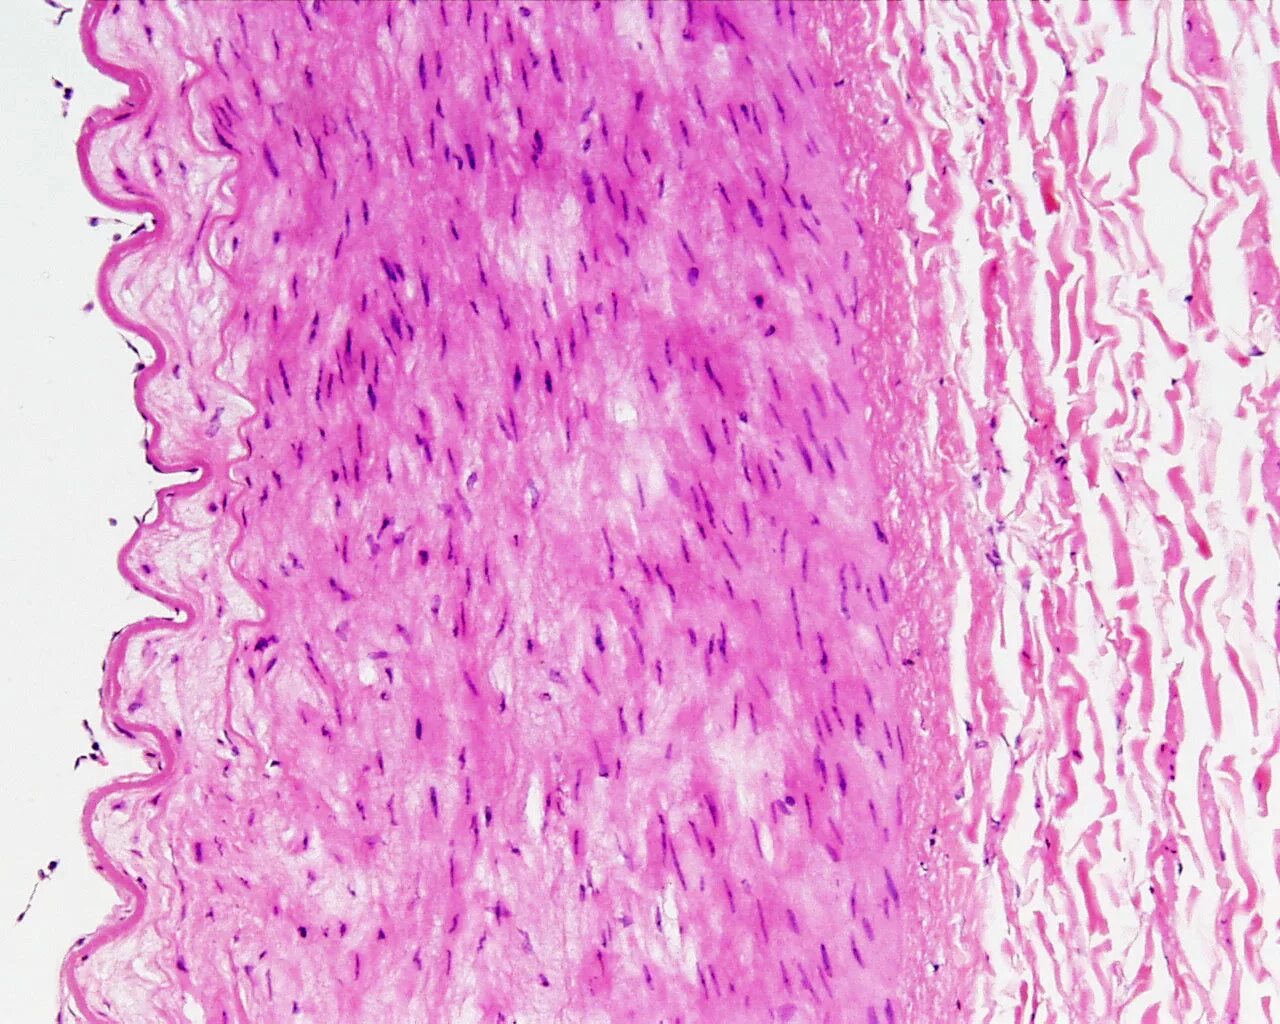

Гистологический срез это